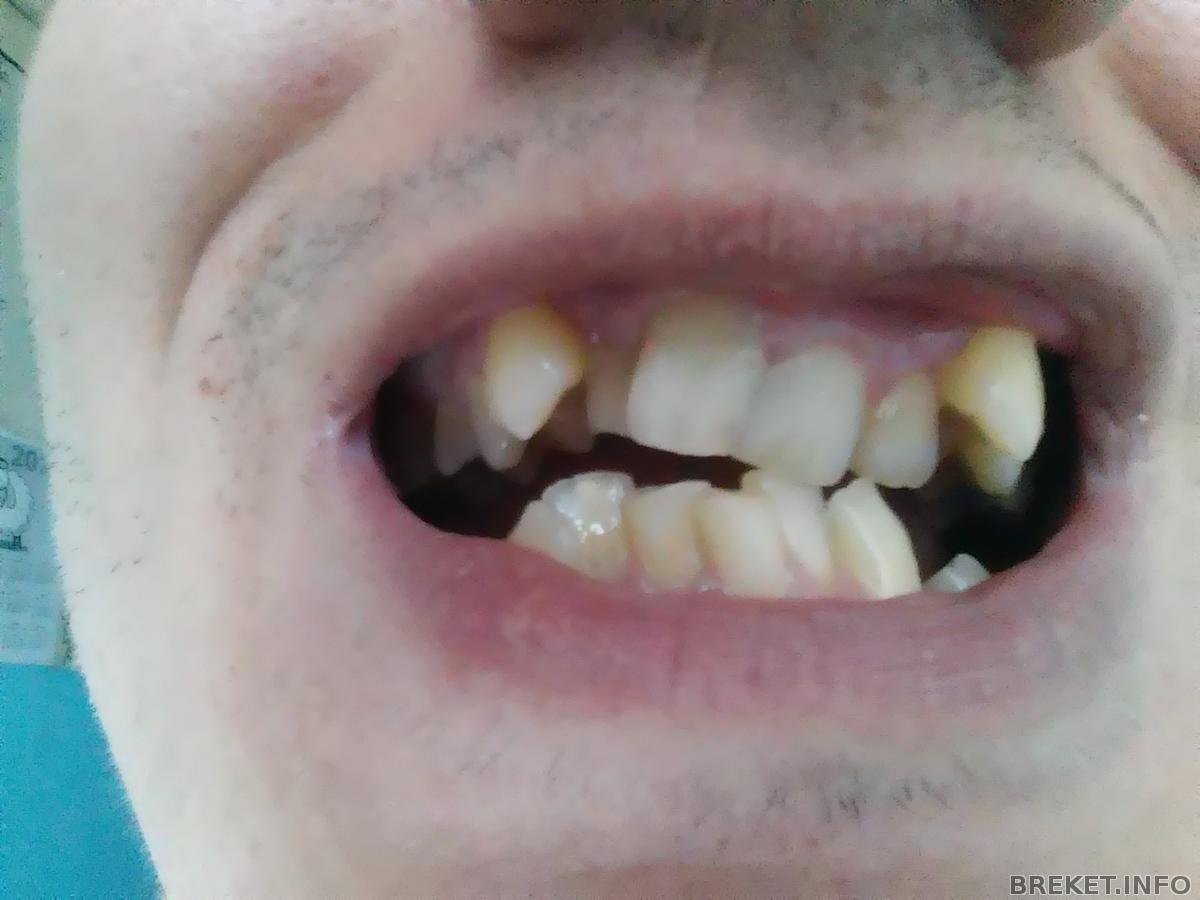

Так мои зубы выглядят при разомкнутых челюстях.

Верхняя челюсть (видны сепараторы)

Нижняя челюсть (заметны промежутки из-за удаленных 4-ок)